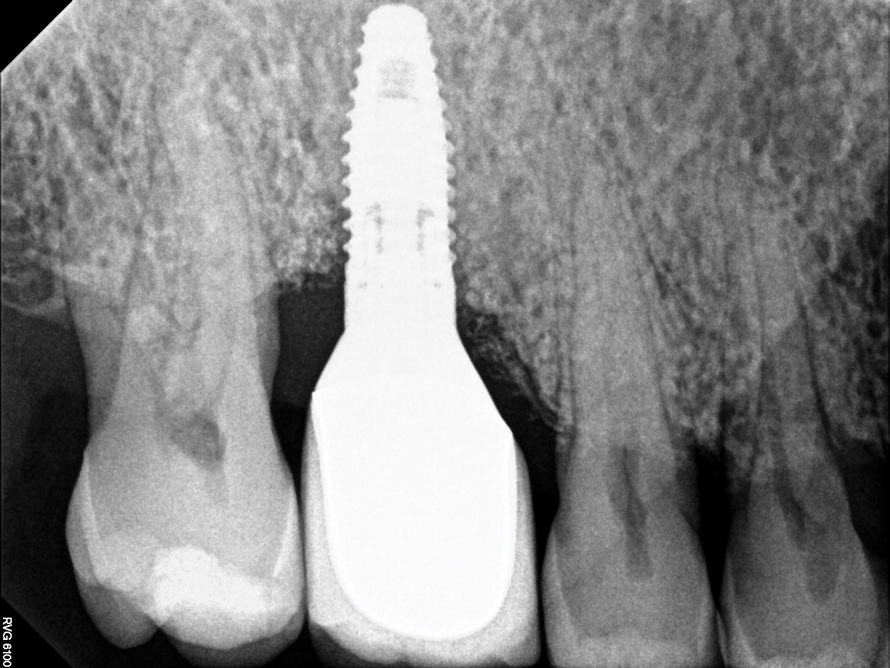

Following the diagnosis of peri-implantitis (Figure 5 and Figure 6), an initial evaluation of the affected implant fixture should be made to establish the rationale for treatment and whether removal of the implant is indicated. Although nonsurgical treatment of peri-implantitis may not always be successful, it should always precede surgical therapy, as this will provide the clinician time to assess the patient's oral hygiene status and response to therapy.22 The primary goal of surgical treatment of peri-implantitis is the decontamination of the denuded implant surface. Multiple surface decontamination protocols have been described in the literature; however, to date, none have shown superiority.23

After implant surface decontamination, the specific surgical approach (eg, access surgery, respective, or regenerative) for each case is heavily dependent on the position of the implant in the oral cavity, as well as the configuration of the peri-implant defect (Figure 7).24 In a recent meta-analysis, an average 2 mm to 3 mm peri-implant probing depth reduction was achieved following surgical intervention.25 Also, implant surface modification (implantoplasty) (Figure 8) was superior to access flap alone. The addition of bone grafts yielded an average of 2 mm of bone fill in defects treated with a regenerative approach. Regenerative treatments may be contraindicated in smokers.

Fig 6. Radiographic bone loss confirmed the diagnosis of peri-implantitis.

Figure 6